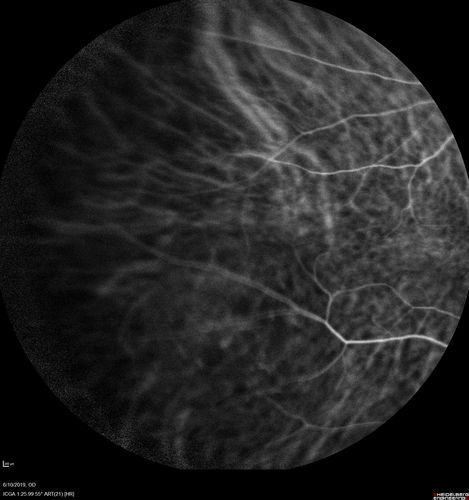

88 year old female with 2.5 mm elevated choroidal melanoma and melanosis oculi.  She also has geographic atrophy from AMD.  The right eye is the better eye with 20/40 vision.  After observation with growth, brachytherapy was done.

Melanosis Oculi and Choroidal Melanoma